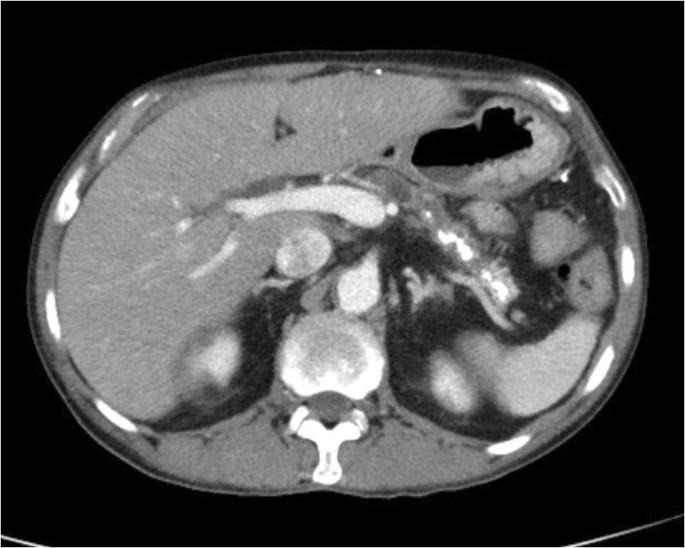

. What is the ICD-10 code for abnormal brain MRI. Abnormal CT scans of the abdomen and pelvic region are often caused by appendicitis. Abnormal computerized tomography of.

Nonspecific abnormal findings on radiological and other examination of abdominal area including retroperitoneum approximate match This is the official approximate match mapping between ICD9 and ICD10 as provided by the General Equivalency mapping crosswalk. The ICD-10-CM code R935 might also be used to specify conditions or terms like abdominal aortogram abnormal abnormal radionuclide scan computed tomography result abnormal computed tomography result abnormal ct of abdomen abnormal ct of abdominal wall abnormal etc. R0989 Abnormal chest sounds R100 Acute abdomen I213 Acute MI unspecified B20 AIDSsymptomatic HIV disease R4182 Altered mental status AMS I209 Angina NOS.

Tumors aneurysms and bleeding are all possible causes of an abnormal CT of the head or brain. ICD-10-CM Diagnosis Code R935 convert to ICD-9-CM Abnormal findings on diagnostic imaging of other abdominal regions including retroperitoneum. M703 Bursitis elbow NEC.

Other possible causes of abnormal results can include. BW21ZZZ is a valid billable ICD-10 procedure code for Computerized Tomography CT Scan of Abdomen and Pelvis. R935 - Abnormal findings on diagnostic imaging of other abdominal regions including retroperitoneum answers are found in the ICD-10-CM powered by Unbound Medicine.